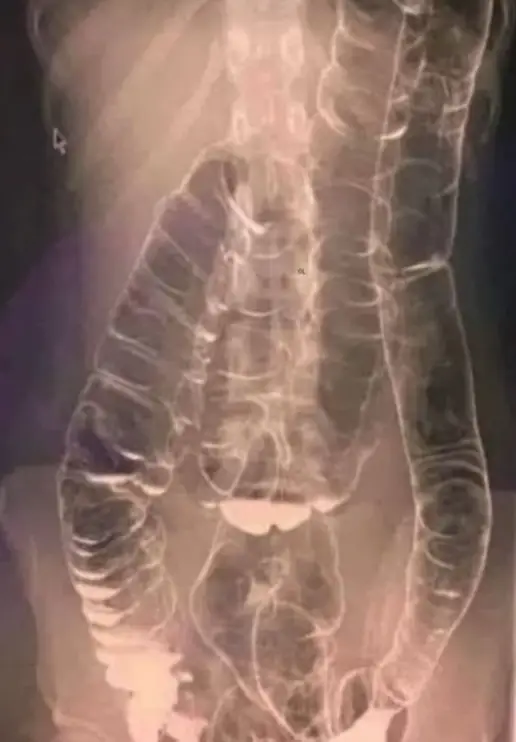

Una impactante radiografía de una mujer que sufrió estreñimiento durante dos semanas conmocionó a los médicos.

Incapaz de acomodar la acumulación excesiva de desechos, su colon se agrandó significativamente, llegando hasta el pecho y cerca del corazón.

El estreñimiento crónico provocó que los pliegues del colon, vitales para su funcionalidad, desaparecieran.